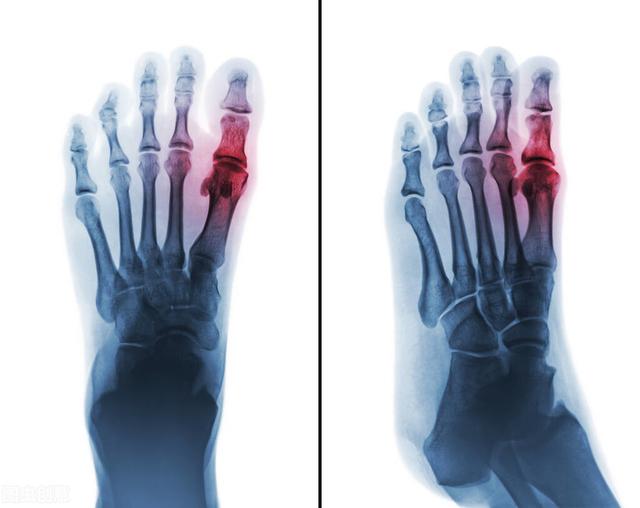

Les parents de l'enfant ont déclaré que le gros orteil de l'enfant avait commencé à lui faire mal après qu'il se l'était tordu. Lorsque j'ai examiné l'enfant, j'ai remarqué que son gros orteil était particulièrement gonflé, bien plus que sur la photo ci-dessus. À ce moment-là, cela ne ressemblait pas du tout à un gonflement dû à une entorse.

Tout d'abord, la goutte est causée par un trouble du métabolisme de la purine entraînant un taux anormal d'acide urique, de sorte que le dépôt d'acide urique dans les articulations se localise pour former des cristaux d'urate, ce qui induit une inflammation locale, provoquant la destruction des tissus et déclenchant la douleur. Donc.Le développement de la goutte est étroitement lié à des anomalies de l'acide urique.

En fait, il s'agit d'un dépôt important d'acide urique dans l'organisme qui ne peut pas être évacué de l'organisme, surtout déposé dans les articulations osseuses, certaines articulations étant faciles à bouger. Le dépôt d'acide urique, un grand nombre de globules blancs sur la résistance, il va produire une inflammation, qui se manifeste par des douleurs, des rougeurs et des gonflements. Dans les cas les plus graves, il est impossible de marcher, et même la formation de calculs de goutte.